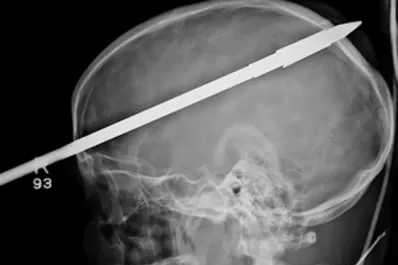

Un arpón atravesó su cabeza y sobrevivió

Un joven de 16 años se lo clavó accidentalmente.